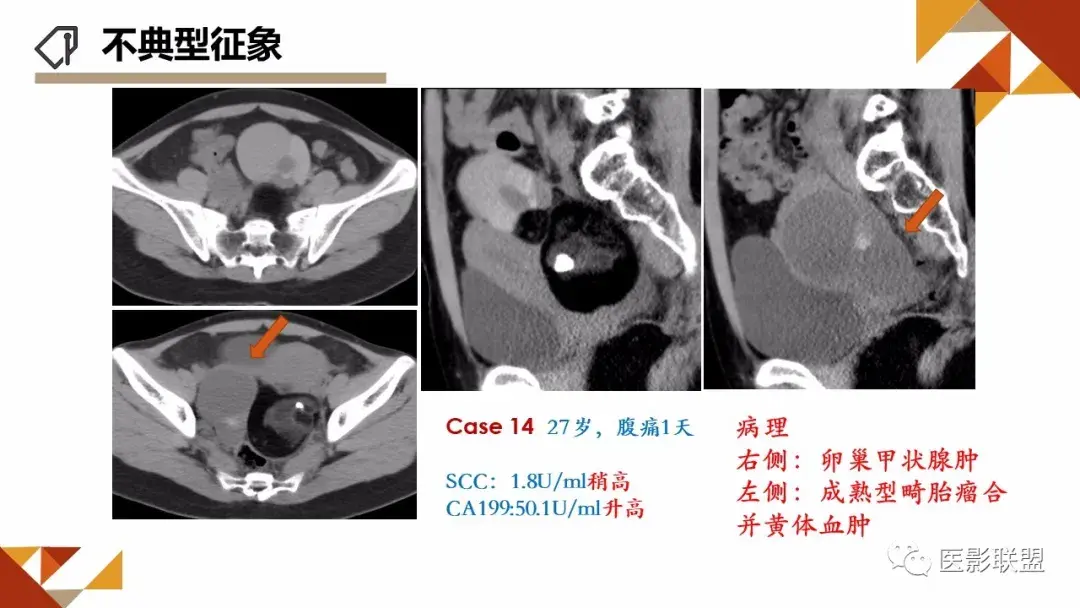

卵巢畸胎瘤的图像诊断及不典型征象分析

作者:刘红艳 清远市人员医院